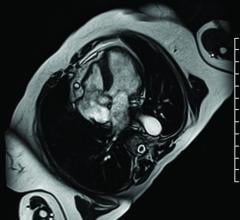

At RSNA 2016, Siemens Healthineers unveiled its groundbreaking Compressed Sensing technology, which overcomes a major ...